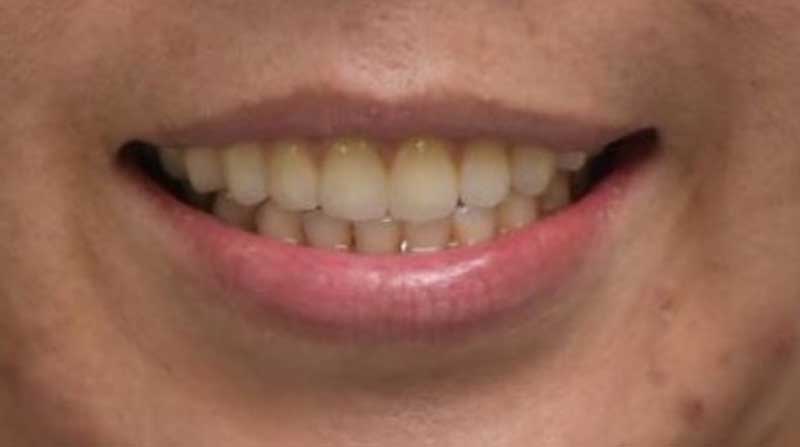

一位40歲的口腔癌患者許小姐,於2024年至中山醫學大學附設醫院口腔顎面外科就醫,該名患者罹患上顎牙齦癌,需手術切除大範圍上顎骨,不僅影響外觀,口內鄰近腫瘤的10顆牙齒亦需一併切除。術前運用電腦數位模擬技術,精準規劃腫瘤切除範圍及術後牙齒重建位置,並模擬將植體植入顴骨中,以彌補上顎骨缺損。手術當日,由中山附醫口腔顎面外科邱昱瑋主治醫師、陳怡孜主治醫師及陳珮吟主治醫師組成的醫療團隊主導,採用電腦數位模擬手術,先模擬腫瘤切除範圍,再模擬出切除後牙齒該有的排列位置,另外,關於上顎骨先前已被部分切除,透過電腦模擬將植體植入顴骨當中;手術當下,結合切割導版與電腦導航系統輔助,所有相關手術程序於同一日一次完成,精準完成上顎口腔癌腫瘤切除、頸部淋巴清除、顴骨植牙及游離皮瓣重建,大幅縮短治療時程,降低患者身體負擔,目前患者許小姐已成功恢復正常咀嚼功能,生活品質大幅提升。